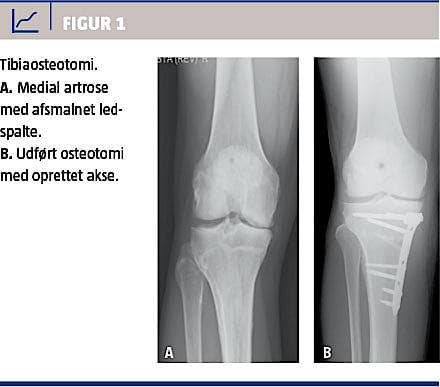

Osteotomi

Osteotomi kan udføres ved let til moderat artrose isoleret til det mediale eller laterale kammer. Behandlingen tilsigter at flytte belastningen til det ikkeafficerede ledkammer, hvorved patientens symptomer bedres. Figur 1 viser et tilfælde af isoleret medial

etkammerartrose, der er behandlet med proksimal

tibiaosteotomi.